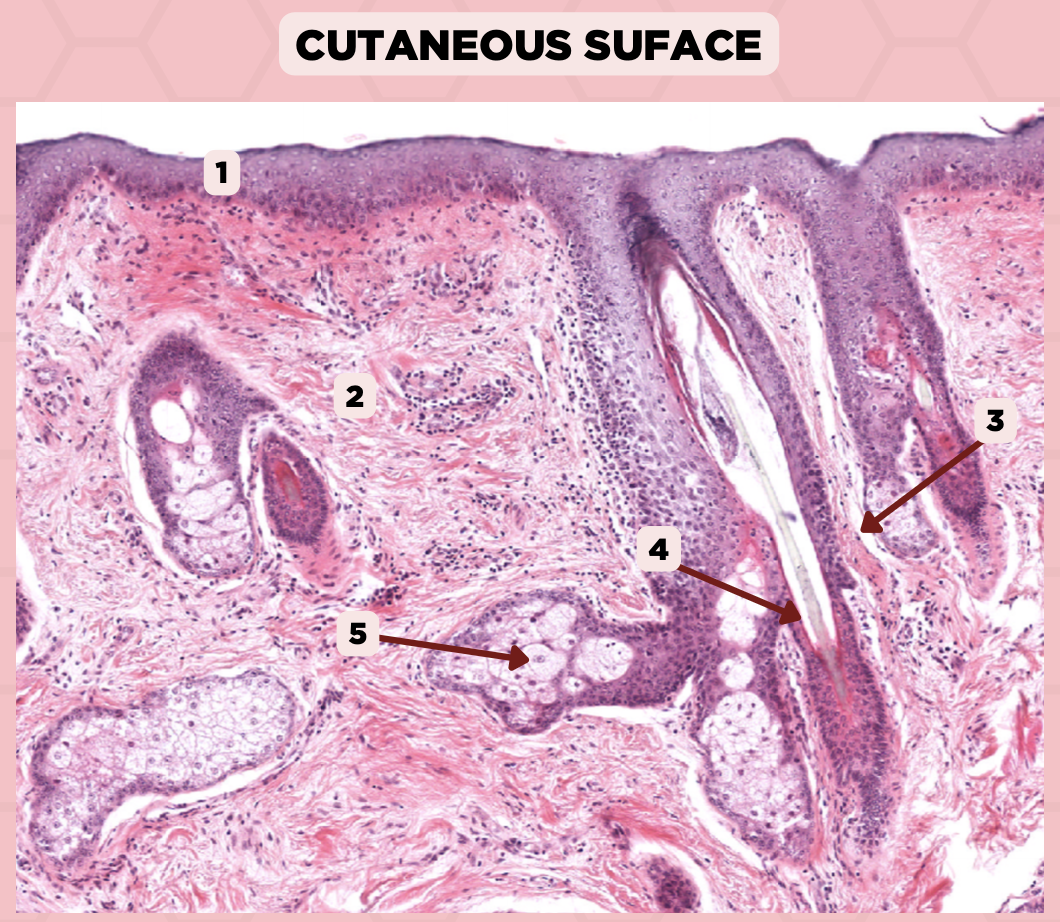

Lip

What is the specimen showed in the picture?

Epidermis

Identify the structure labeled as 1.

Dermis

Identify the structure labeled as 2.

Arrector Pilli Muscle

Identify the structure labeled as 3.

Hair Follicle

Identify the structure labeled as 4.

Sebaceous Glands

Identify the structure labeled as 5.